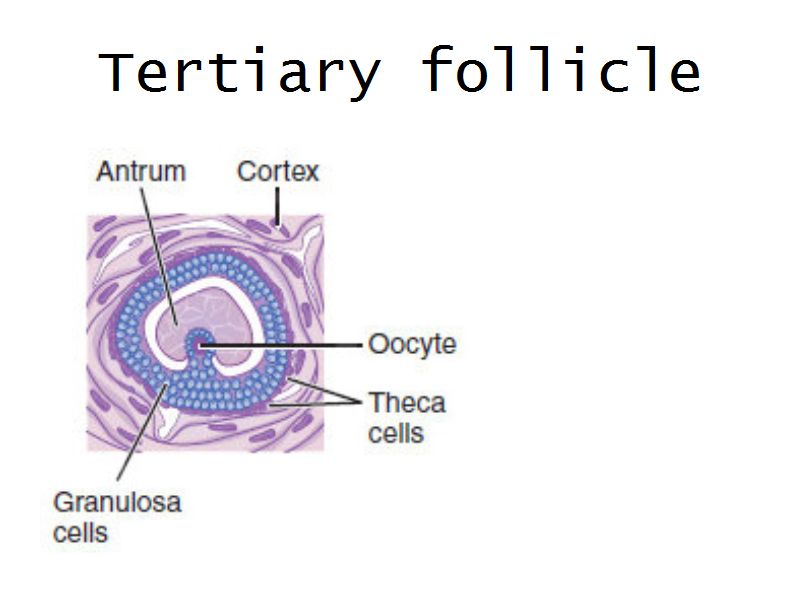

Follicular maturation

- Primordial follicle

- Growing follicle

- Primary follicle

- Secondary follicle

- Mature follicle (Graafian)

Components of a follicle

- Theca

- externa

- interna

- basal lamina

- Granulosa cells

- Antrum

- Cumulus oophorus >> Corona radiata

- Oocyte